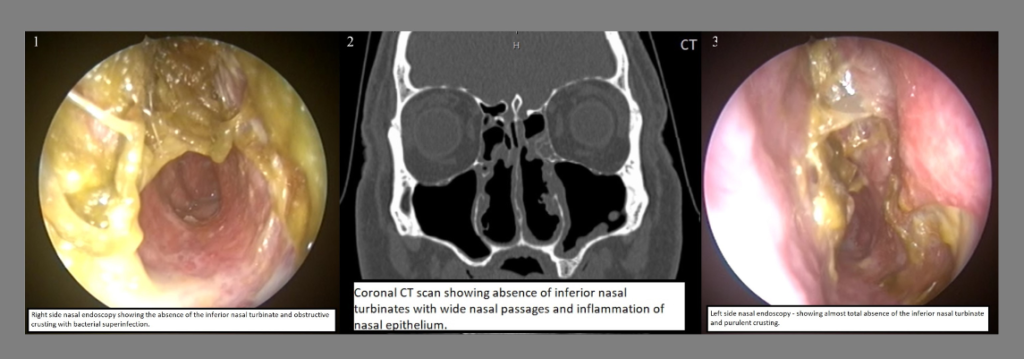

A physical examination of the nasal cavity allows the doctor to assess the condition of the turbinates and other nasal structures. During this examination, the doctor can evaluate whether the turbinates have been excessively removed, the condition of the nasal mucosa, and the width of the nasal airways. This examination can be enhanced with an endoscopic procedure, allowing detailed visualization of the nasal cavity and detection of abnormalities in the nasal tissues.

Imaging Techniques:

In some cases, the doctor may order a CT scan (computed tomography) or MRI (magnetic resonance imaging) to better assess the structure of the nose and sinuses. These imaging techniques can provide detailed views of the structural changes in the nose and the condition of the turbinates. These tests can also help differentiate ENS from other causes of nasal obstruction.